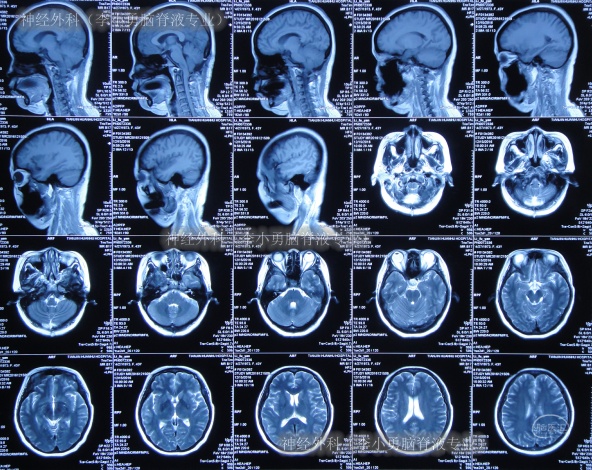

二、神经外科(李小勇脑脊液专业)治疗过程和结果

2017年1月9日(后颅窝减压术枕大池成形术62天,发热伴头痛近2月,腰大池引流术后18天,枕部皮下积液9日)住入李小勇脑脊液专业,入院时:间断高热,剧烈头痛,后颅窝疼痛更重,携带外院腰大池引流管,引流管壁内有脓性脑脊液,引流出的脑脊液浑浊;后颅窝术后有积液(图-10)。

图-10:2017年1月9日入院时

入院时查头颅CT示后枕部颅骨缺损,头皮膨出,皮下有积液,触之波动感(图-11)。

图-11:2017年1月10日头颅CT

入院后3天即2017年1月12日,拔除了原外院腰大池引流管+脑室腹壁外引流术(图-12)。

图-12:2017年1月12日头颅CT

住院后7天即2017年1月16日,头痛减轻,引流出的脓性脑脊液消失(图-13)。

图-13:2017年1月16日